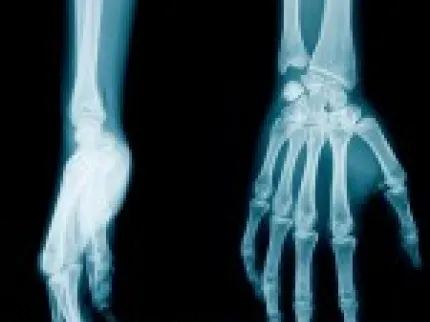

Image

Radio de la main